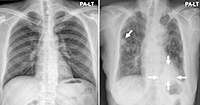

3. 흉부 X선

흉부 X선은 만성 폐쇄성 폐질환의 진단 과정에서 다른 질환(예: 폐암, 심부전)을 배제하는 데 사용됩니다. 흉부 X선만으로 만성 폐쇄성 폐질환을 확진할 수는 없지만, 폐의 과팽창이나 횡격막 평탄화와 같은 질환과 일치하는 변화를 확인할 수 있습니다.